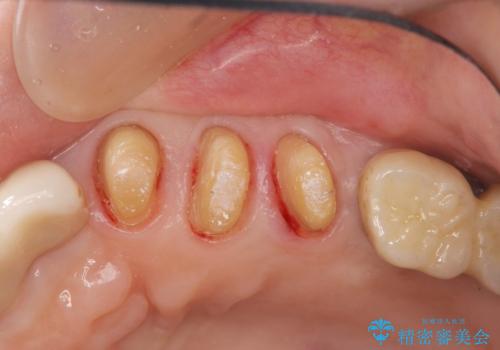

- 夜間のくいしばり、はぎしりが激しく全体的な歯周病が進行し、治療を希望され来院されました。

歯周ポケットの徹底的な除去を行なったのち、歯の揺れを抑え、過大な力がかからぬよう連結クラウン(歯周補綴)を行い強大な力に対抗します。